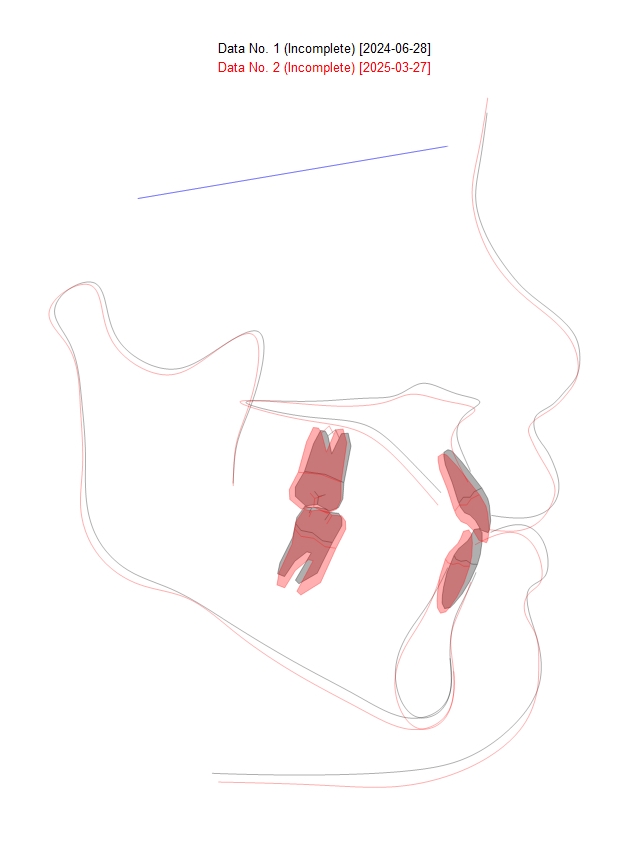

아래 그림은 치료 시작 전 및 최근 엑스레이 사진을 중첩한 것으로, 치료 전에 비하여 아래 앞니 공간이 닫히며 뒤로 후방이동하면서 아래 입술도 1mm 정도 들어간 것을 확인할 수 있습니다.

엑스레이 중첩 (superimposition)